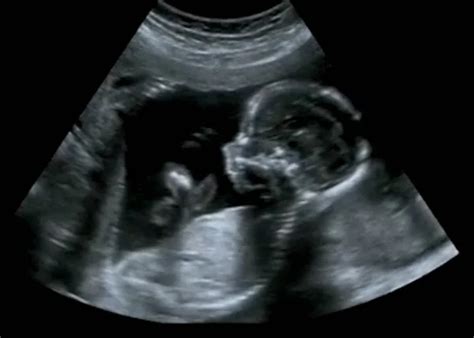

Az első genetikai szűrővizsgálat a 12. hét körül történik. A Down-szindróma vizsgálatát a protokoll szerint a 11-13. hét között végzik, leggyakrabban a 12. héten. Ez az időpont azonban eltérhet a változó időben bekövetkező ovuláció miatt. A nyaki redő vastagságának mérése 14 hetesen már értékelhetetlen lehet, ezért fontos, hogy a vizsgálat időben megtörténjen.

Egyes esetekben a helyi főorvos vérvételből és ultrahangból javasolhatja a Down-szindróma vizsgálatát már korábbi terhességi héten. Azonban egy 8 hetes magzatnál a nyaki redő mérése nem lehetséges.

A protokoll szerint élő terhességgel küldik a kismamát a védőnőhöz, ami azt jelenti, hogy a magzatnak már hallható a szívhangja. Öthetesen ez általában még nem jellemző, de 5-8 hetesen már sok esetben hallható a szívhang. A várandósgondozás akkor kezdődik, amikor a szülész-nőgyógyász szakorvos megállapítja a méhen belüli terhességet és elvégzi a rizikó-besorolást.